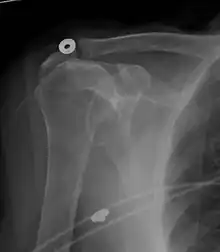

Projectional radiograph of normal glenohumeral position.[47]

High-riding humeral head in a rotator cuff tear.

X-ray projectional radiography cannot directly reveal tears of the rotator cuff, a 'soft tissue', and consequently, normal X-rays cannot exclude a damaged cuff. However, indirect evidence of pathology may be seen in instances where one or more of the tendons have undergone degenerative calcification (calcific tendinitis). The humeral head may migrate upwards (high-riding humeral head) secondary to tears of the infraspinatus, or combined tears of the supraspinatus and infraspinatus.[47] The migration can be measured by the distance between:

• A line crossing the center of a line between the superior and inferior rims of the glenoid articular surface (blue in image).

• The center of a "best-fit" circle positioned over the humeral articular surface (green in image)

Normally, the former is positioned inferiorly to the latter, and a reversal is therefore indicating a rotator cuff tear.[47] Prolonged contact between a high-riding humeral head and the acromion above it, may lead to X-rays findings of wear on the humeral head and acromion and secondary degenerative arthritis of the glenohumeral joint (the ball and socket joint of the shoulder), called cuff arthropathy, may follow.[46] Incidental X-ray findings of bone spurs at the adjacent acromioclavicular joint may show a bone spur growing from the outer edge of the clavicle downwards towards the rotator cuff. Spurs may also be seen on the underside of the acromion, once thought to cause direct fraying of the rotator cuff from contact friction, a concept currently regarded as controversial.